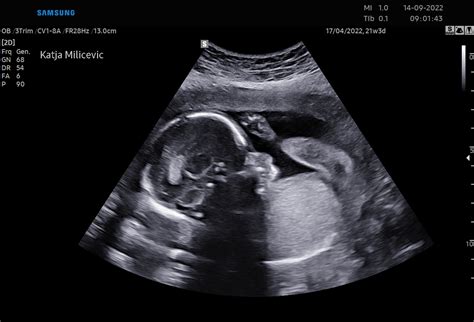

V 21. tednu nosečnosti plod doseže dolžino približno 26,7 cm in težo okoli 360 gramov. V tem obdobju se nadaljuje intenziven razvoj čutil. Čeprav še ne uporablja vonja in okusa v svojem "domu", se ti čuti še naprej razvijajo. Aminotska tekočina, ki ga obdaja, prenaša aromatične molekule iz hrane, ki jo mati uživa, ter vonje iz okolja. To pomeni, da bo otrok že ob rojstvu privlačil vonj materine kože in mleka, ter sladkast okus plodovnice.

Njegovi možgani postajajo dovolj zreli, da si lahko te čutne izkušnje zapomnijo. V črevesju se formira prvo blato, imenovano mekonij, in prične delovati plodov lastni imunski sistem. Oči so razvite, čeprav so še vedno zaprte. V primeru prezgodnjega rojstva v 22. ali 23. tednu plod že ima možnost preživetja zunaj maternice, kar poudarja napredek v razvoju organov in živčevja. V 23. tednu plod meri približno 28,9 cm in tehta okoli 501 gram.

Teža in velikost otroka v maternici ni statična, temveč se spreminja iz tedna v teden. V 21. tednu nosečnosti je otrok primerljiv po velikosti s korenčkom. Kot je navedeno v forumski izmenjavi, je pri 21 tednih in 5/7 dneva nosečnosti, glede na meritve BPD (biparietalni premer) 51,8 mm in AC (abdominalni obseg) 195 mm, teža lahko ocenjena na približno 360 gramov. V drugem primeru, nosečnica v 21 tednih in 3/7 dneva nosečnosti poroča o oceni teže 490 g, kar je nekoliko več od pričakovane.

Pomembno je poudariti, da te meritve predstavljajo le oceno. Kot je pojasnil dr. Pušenjak, so formule za izračun teže zapletene in se v klinični praksi uporabljajo tabele, ki upoštevajo kombinacije mer, kot sta BPD in AC ali HC (glavni premer) in AC. Poleg tega je teža ploda v zgodnejših obdobjih nosečnosti, kot je 21. teden, še vedno precej irelevantna za oceno prihodnje rasti.